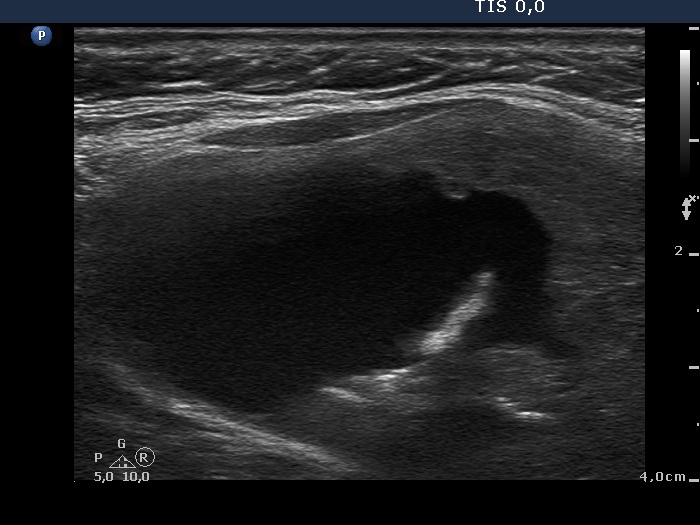

Benign colloid goiter (cytological diagnosis) - case 1429

The nodule has pale hyperechogenic granules and lines corresponding to the normal architecture of the thyroid consisted of connective tissue.